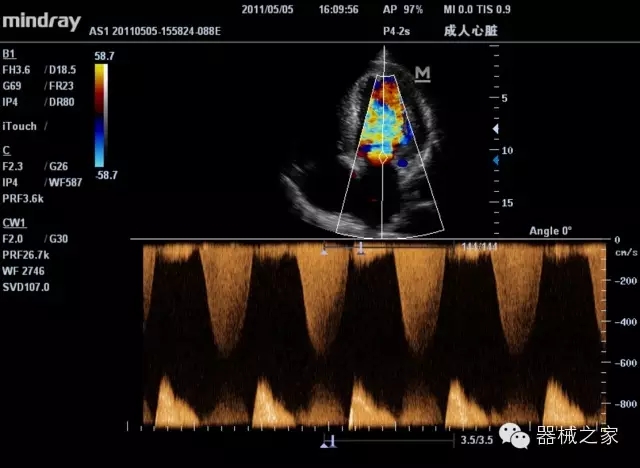

經(jīng)典產(chǎn)品:M7(星鉆)

臨床圖片賞析

產(chǎn)品特點(diǎn)